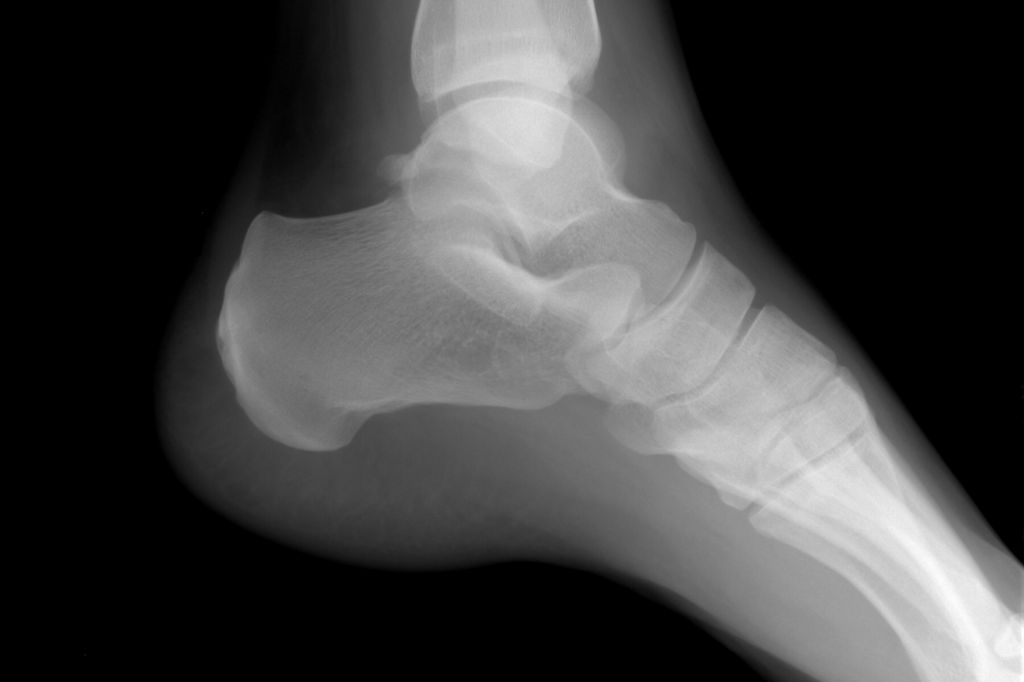

Vývoj tištěného materiálu podobného lidské kosti zabral čtyři roky. Vědci jsou ve fázi, kdy dokončili optimalizaci komerční 3D tiskárny určené k tisku kovových objektů. Nyní je schopna pracovat s práškovým fosforečnanem vápenatým, který je hlavním materiálem na kostní náhrady. Jeho pevnost se teď vědcům podařilo více než zdvojnásobit přidáním křemíku a zinku. Vytištěný kus leží týden v médiu s nezralými kostními buňkami a pak už je připraven k použití.

Když se spojí se skutečnou kostí, funguje jako lešení pro růst nové kosti a nakonec se beze zbytku rozpustí. Je proto vhodný pro ortopedii, zubní lékařství i k „doručování“ léků proti osteoporóze. Velkou výhodou je, že náhrada se dá vytisknout podle potřeb konkrétního pacienta. Stačí, když má lékař k dispozici snímky defektu z výpočetního tomografu. Vědci je převedou do formátu CAD a podle něj na míru vytisknou lešení pro růst nové kosti, která vadnou část nahradí. Materiál úspěšně prošel testy in vitro a také experimenty na pokusných zvířatech vypadají slibně. Vědci proto nevylučují, že vytištěné kostní náhrady budou pacientům k dispozici během několika příštích let.